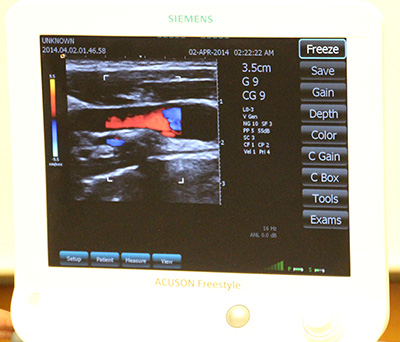

デモンストレーションの様子

画面の右にあるメニューは,プローブから操作可能